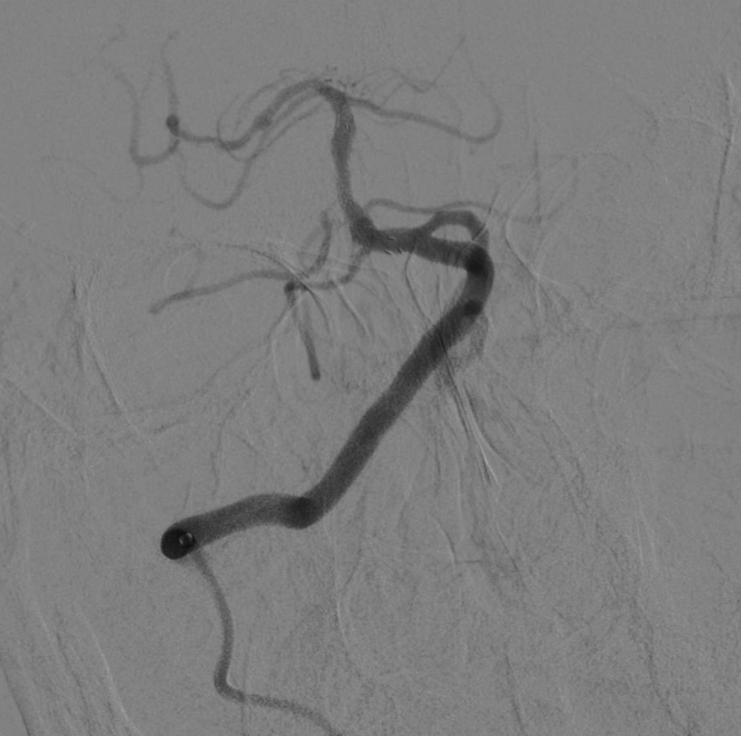

图3:术前造影显示:基底动脉中段重度狭窄,狭窄率95%。

今年12月,王爷爷又因反复头晕回来复查。血管造影提示,基底动脉中段出现了重度狭窄(如图1),血管斑块处于不稳定状态(如图2),就像一颗“定时炸弹”,随时可能再次引发卒中,具备强烈的手术指征。

图1:头颈部CTA:基底动脉重度狭窄。